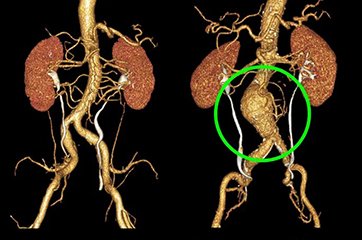

With their state-of-the-art office in the Health City, Arilova, Visakhapatnam, the “Vizag Vascular Center” is an innovative Hospital for comprehensive Vascular care with a world-renowned team of qualified Vascular and Endovascular surgeons, who are recognized as the best in the treatment of Vascular diseases. The team includes highly trained surgeons and physicians dedicated exclusively to the care of disorders of the circulatory system, including the arteries and veins. They help patients optimally manage vascular conditions, whether through diet, exercise and medication, open surgical or minimally invasive interventional procedures.